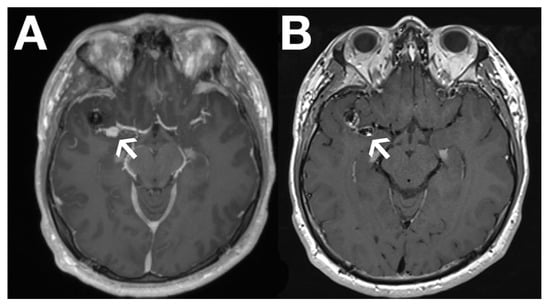

Recently, black blood imaging has made the evaluation of vessel wall enhancement feasible by suppressing the signal from the blood within the vessel itself. This has proven particularly valuable in brain aneurysm (Figure 1) and in cerebral vasculitis assessment.

Figure 1. Images show gadolinium-enhanced T1 (A) and black blood images (B) of a dissection aneurysm following endovascular treatment with a flow diverter of a primary right medial cerebral artery aneurysm. The arrow shows contrast enhancement of the aneurysmal vessel wall on black blood imaging in (B), which cannot be seen on the conventional gadolinium-enhanced T1 image in (A). The finding indicates an unstable aneurysm.